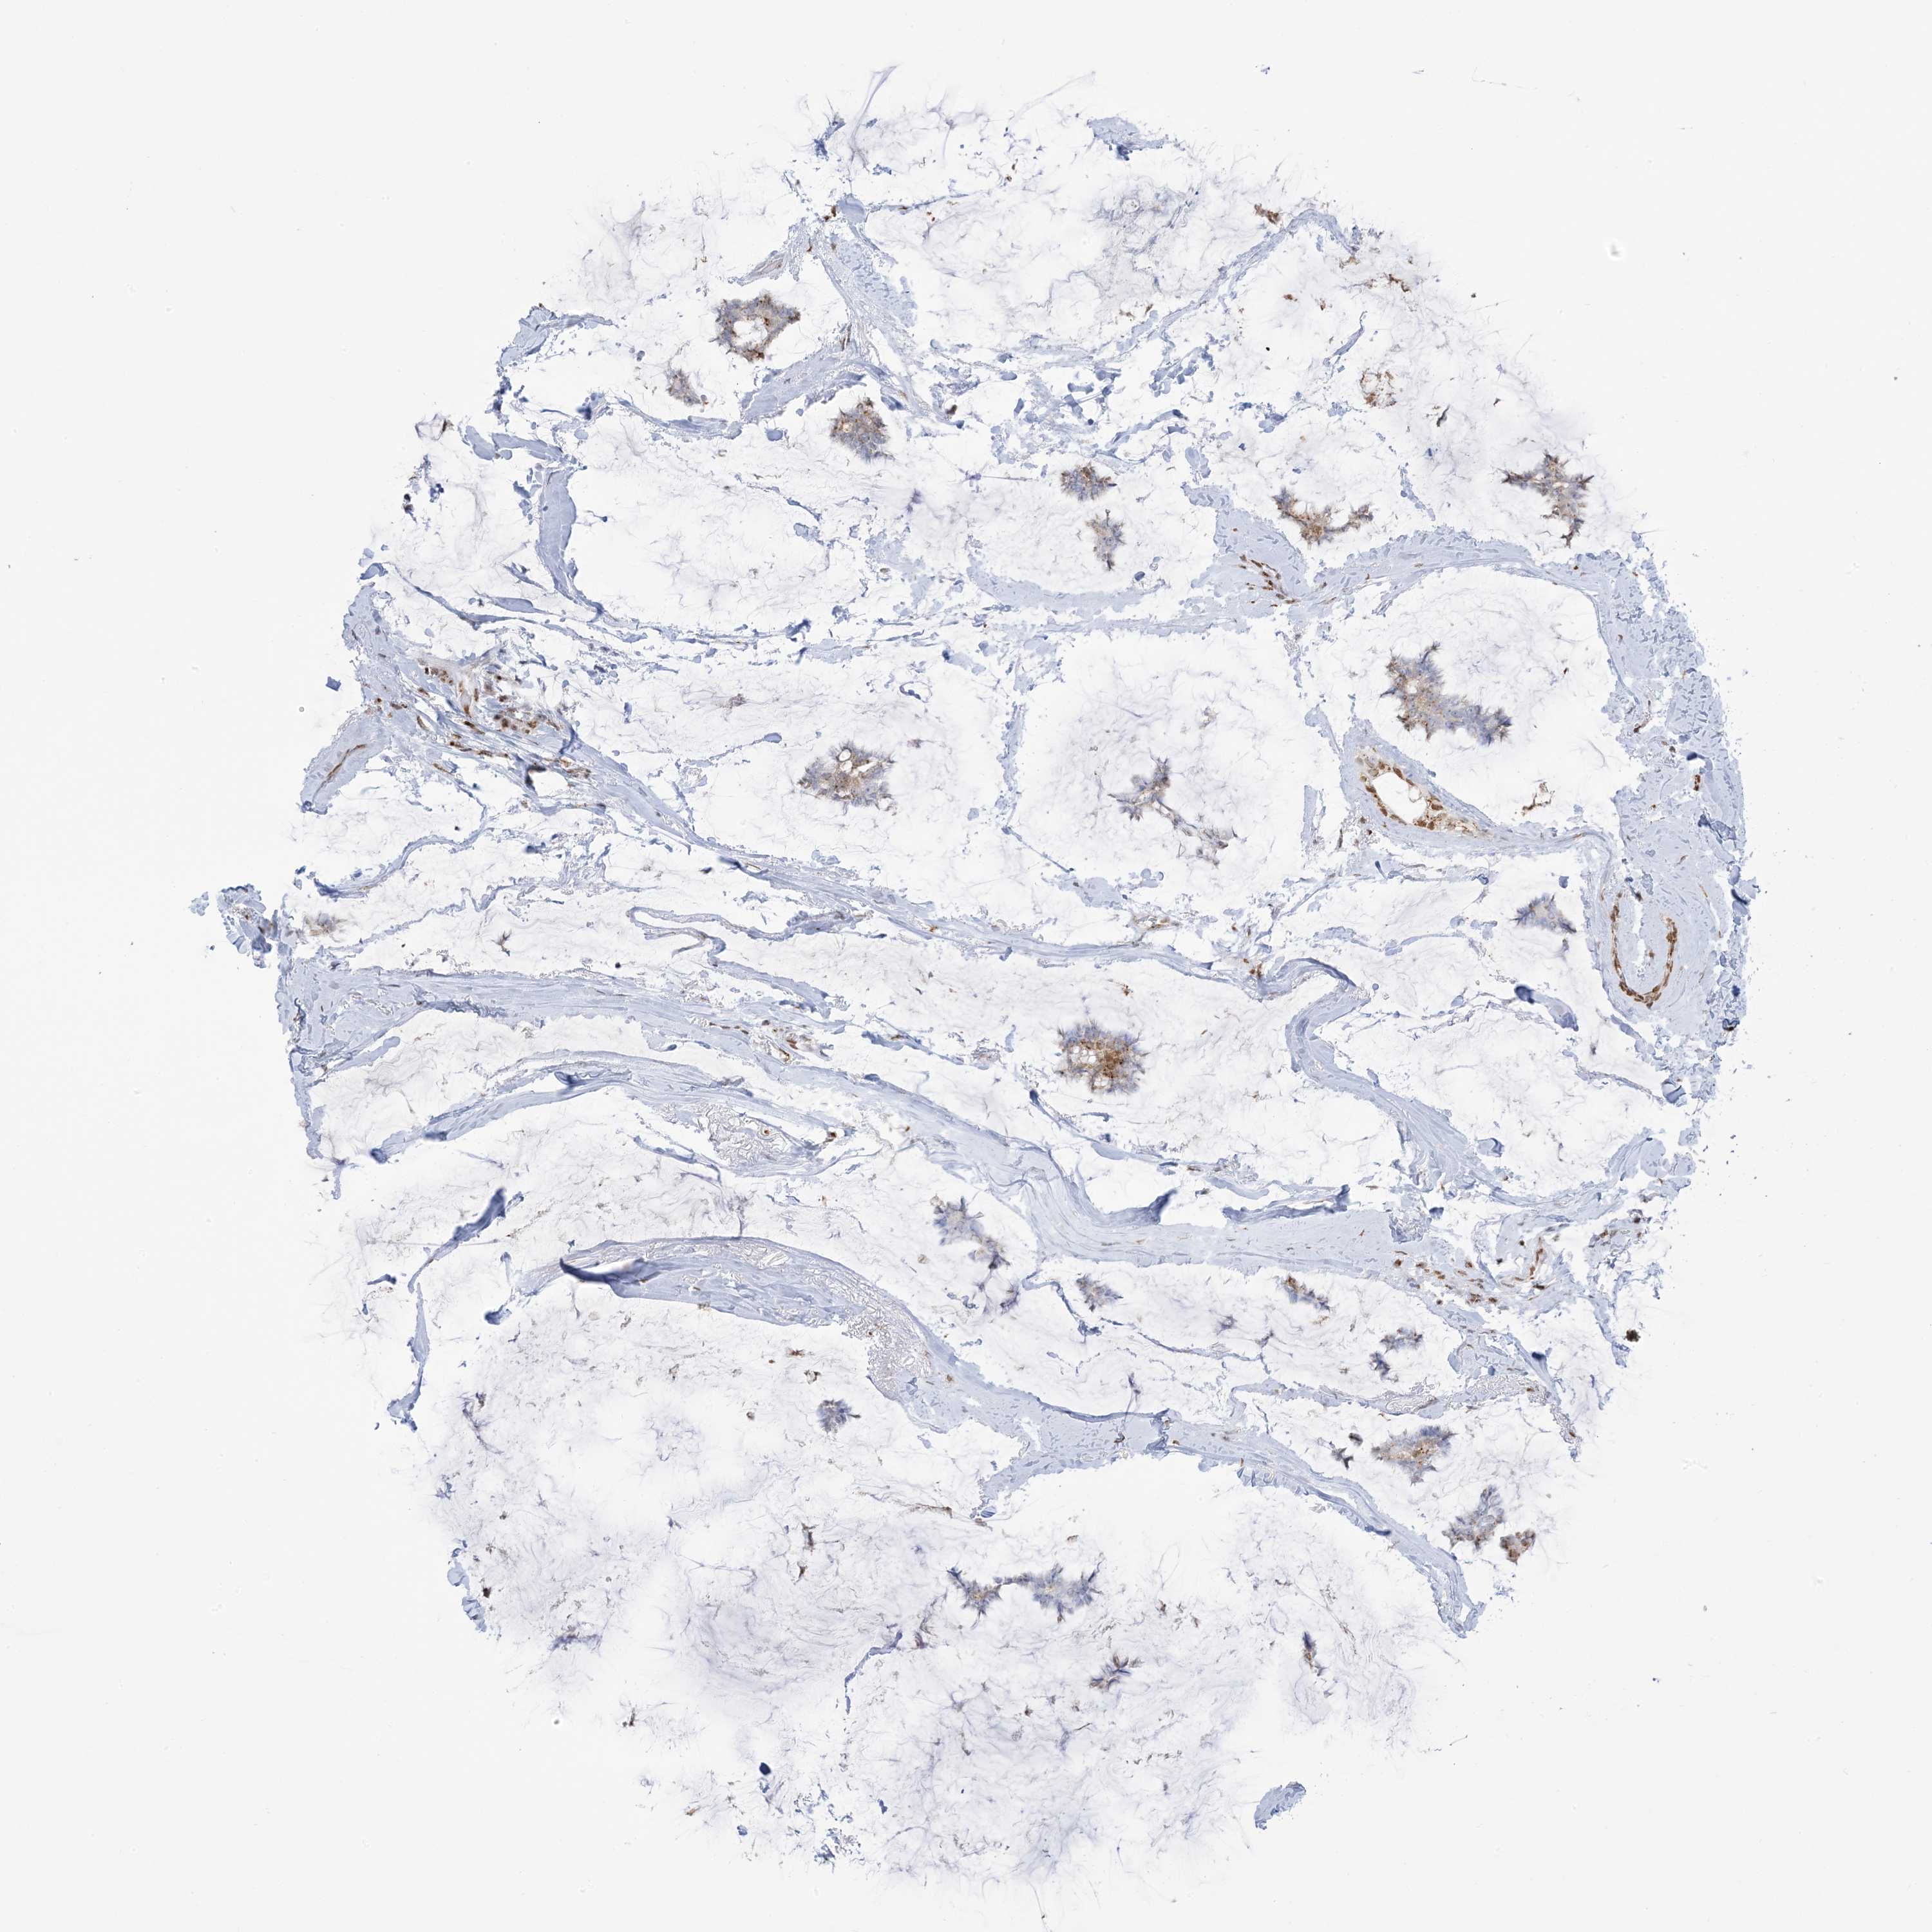

CANCER BREAST CANCER Show tissue menu

BRCA TCGA BRCA VALIDATION PROTEIN EXPRESSION